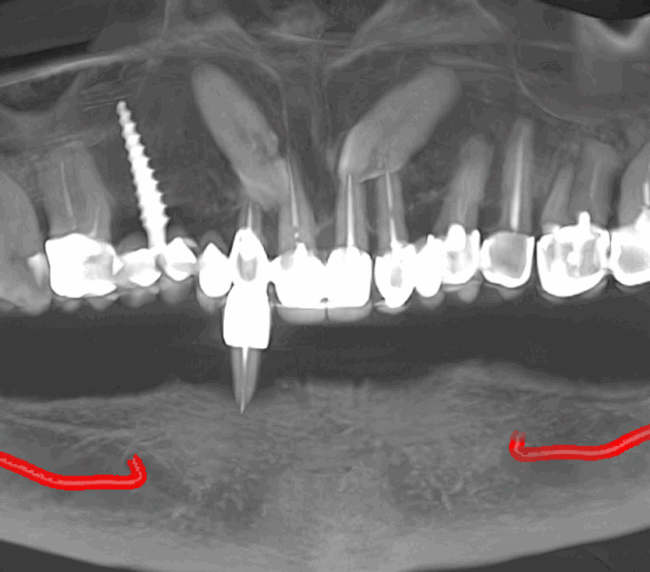

studii științifice.În cazurile de atrofie osoasă severă, când inserarea implanturilor în zonele laterale nu este posibilă fără adăugare osoasă, conceptul All-on-4 prevede plasarea implanturilor în unghiuri strategice pentru a evita zonele deficitare. Astfel, două implanturi sunt plasate în zona incisivilor laterali, iar alte două în zona premolarilor.

- Investigație imagistică completă, ideal CBCT (computer tomografie);